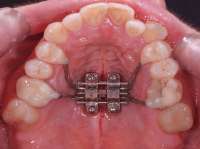

>>1556967